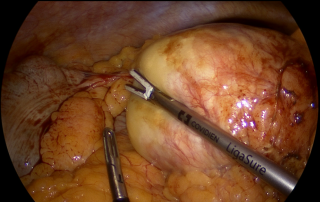

Case presentation

A 55-year-old overweight man presented with one week of right-sided abdominal pain with recent worsening despite outpatient medical therapy. He was hemodynamically stable but had right upper quadrant tenderness and localized guarding. Laboratory testing showed elevated C-reactive protein with a normal leukocyte count and normal liver biochemistry. CT demonstrated inflammatory fat stranding of the right greater omentum with a hyperdense rim, consistent with right-sided omental infarction (Figure 1). Because pain persisted despite conservative management, diagnostic laparoscopy was performed and confirmed ischemic omentum with hemorrhagic peritoneal fluid (Figure 2), and a normal gallbladder and appendix. Laparoscopic omentectomy was completed without complications. Histopathology confirmed omental infarction (Figure 3). The patient was discharged on postoperative day 1 and remained asymptomatic at 6-week follow-up.